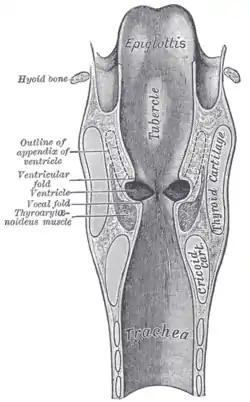

Phonation

Phonation is the production of a periodic sound wave by vibration of the vocal folds. Airflow from the lungs, as well as laryngeal muscle contraction, causes movement of the vocal folds. It is the properties of tension and elasticity that allow the vocal folds to be stretched, bunched, brought together and separated. During prephonation, the vocal folds move from the abducted to adducted position. Subglottal pressure builds and air flow forces the folds apart, inferiorly to superiorly. If the volume of airflow is constant, the velocity of the flow will increase at the area of constriction and cause a decrease in pressure below once distributed. This negative pressure will pull the initially blow open folds back together again. The cycle repeats until the vocal folds are abducted to inhibit phonation or to take a breath.